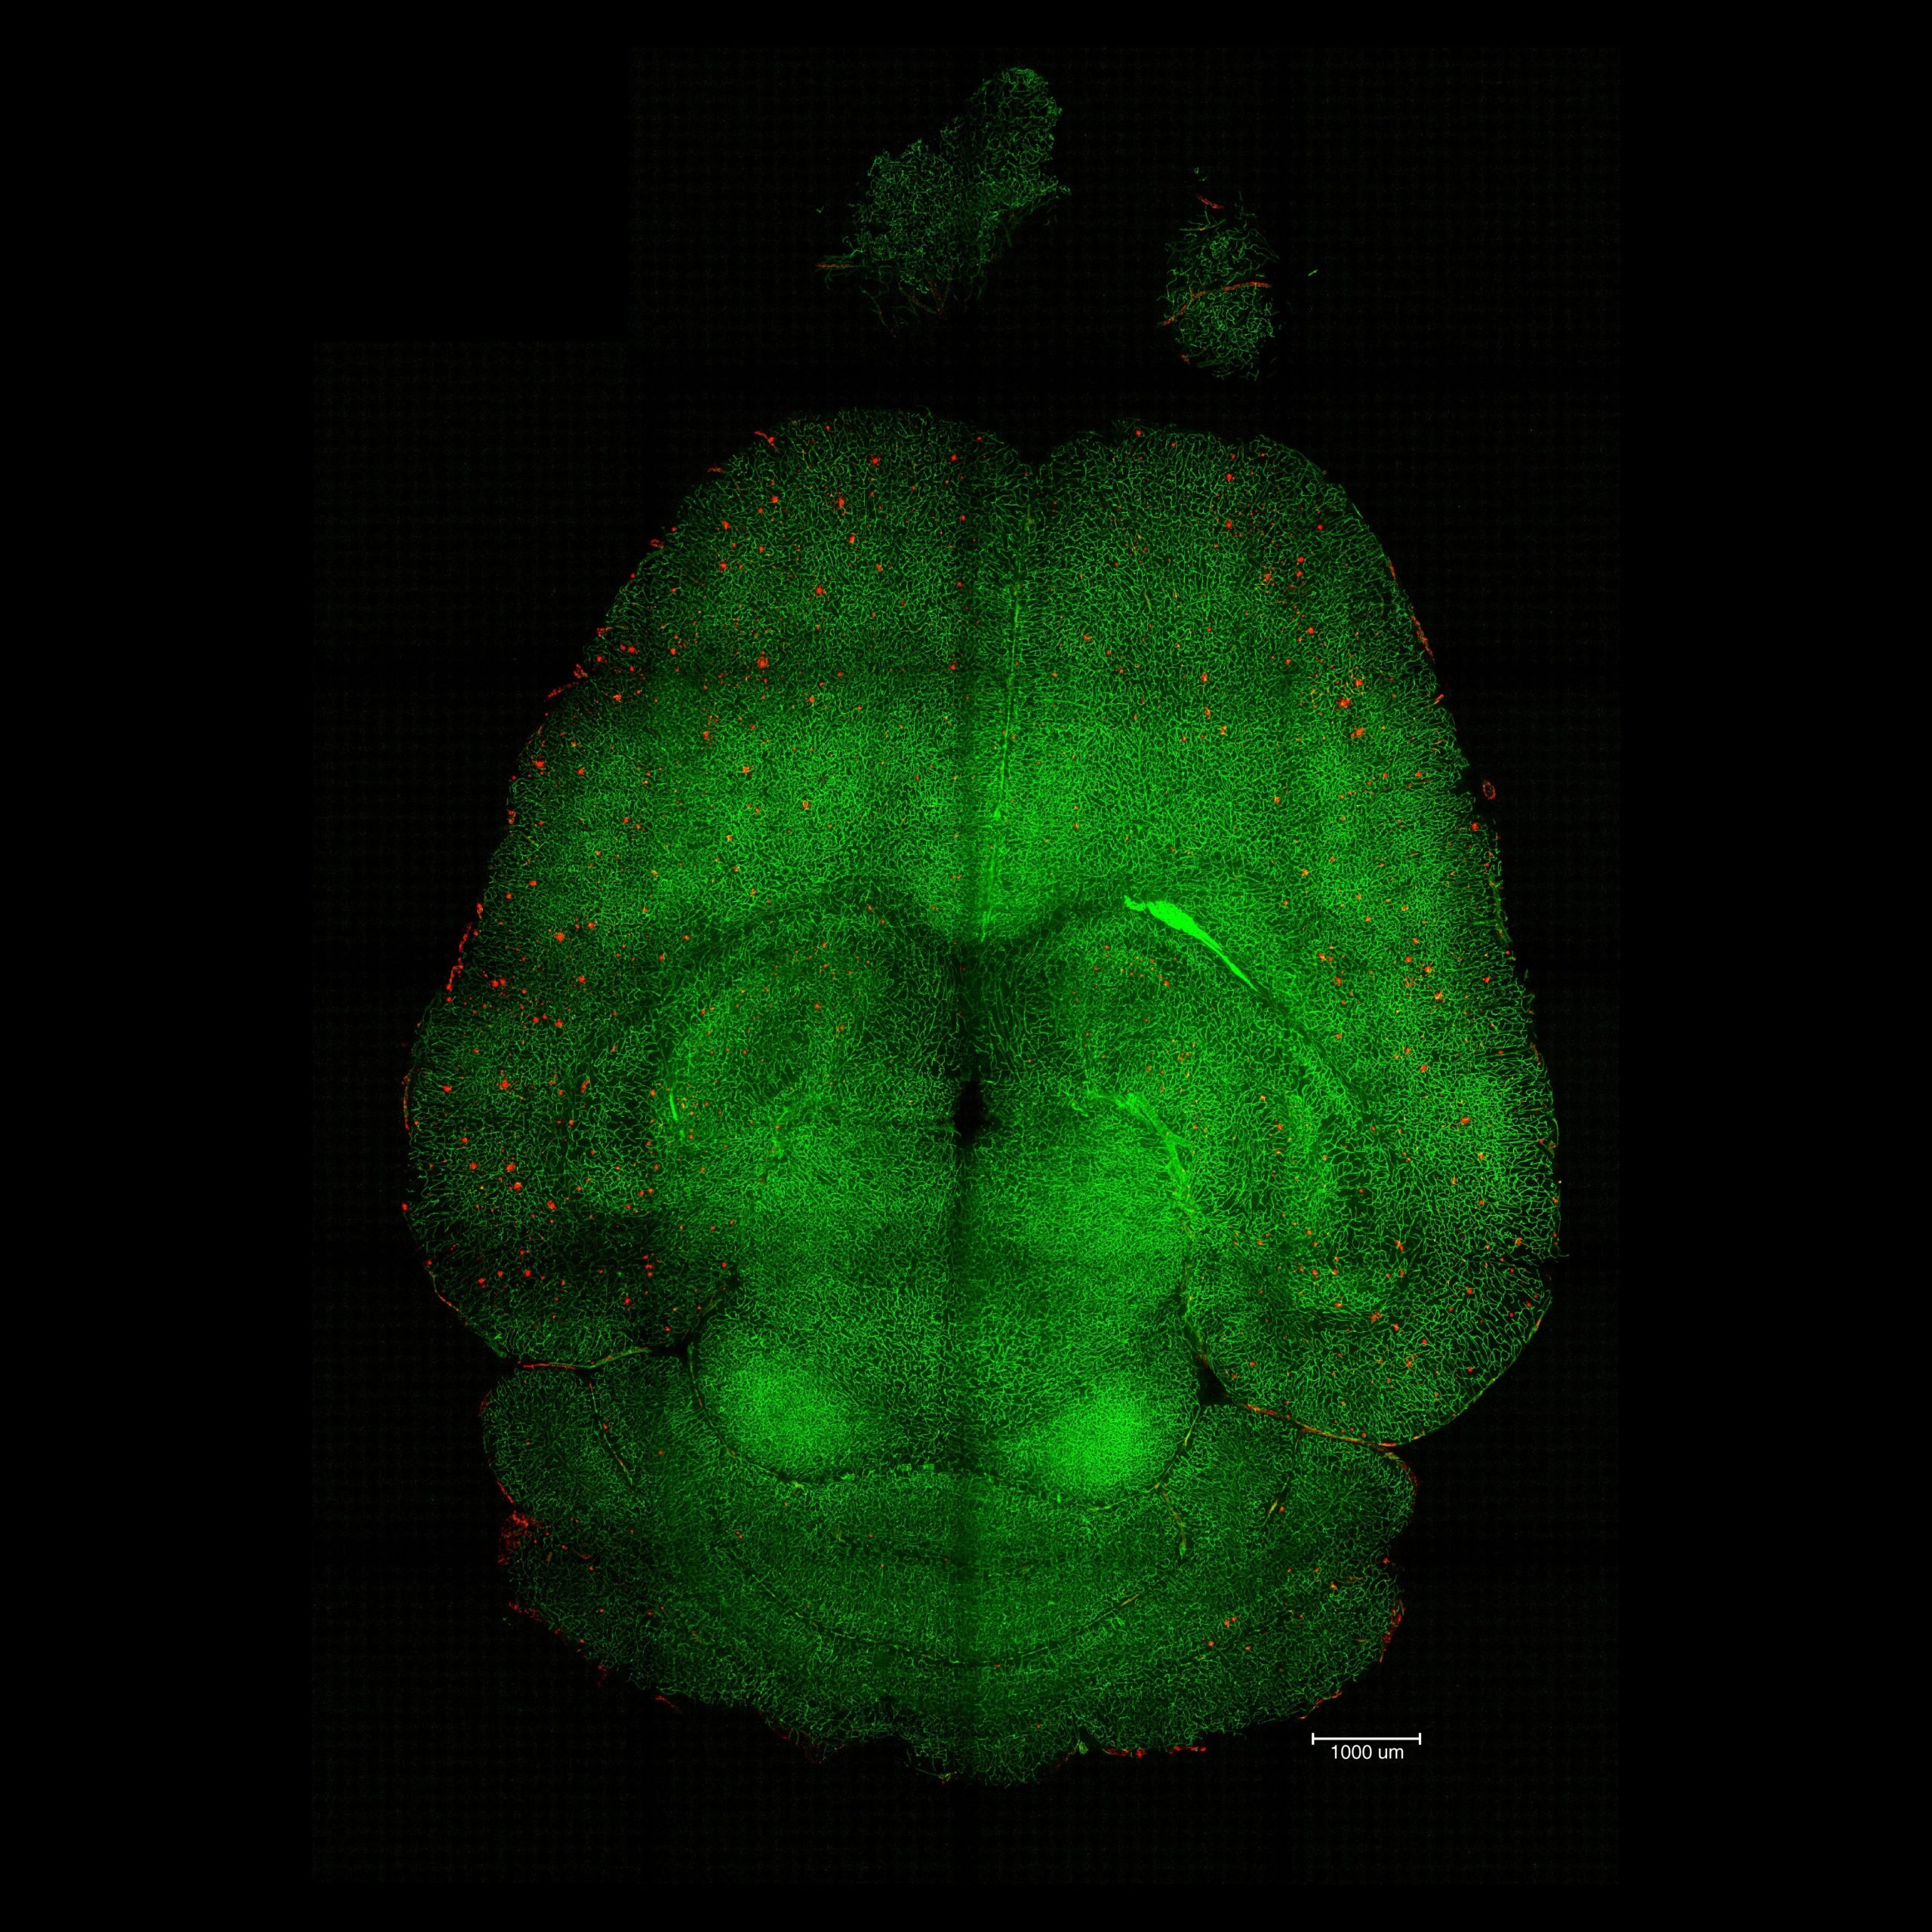

Light sheet fluorescence microscope image of mthe ouse brain 12h after being treated with nanoparticles. The brains were analyzed to see the amount of Aβ plaque accumulation. Red: Aβ plaques. Green: vessels from the blood-brain barrier. Credit: Institute for Bioengineering of Catalonia (IBEC)The most striking data were the therapeutic effects. Researchers conducted various experiments to analyze the behavior of the animals and measure their memory decline over several months, covering all stages of the disease. In one of the experiments, they treated a 12-month-old mouse (equivalent to a 60-year-old human) with the nanoparticles and analyzed its behavior after 6 months. The result was impressive: the animal, aged 18 months (comparable to a 90-year-old human), had recovered the behavior of a healthy mouse.

Light sheet fluorescence microscope images of mouse brain 12h after NOT being treated with nanoparticles. The brains were analyzed to see the amount of Aβ plaques accumulation. Red: Aβ plaques. Green: vessels from the blood brain barrier. Credit: Institute for Bioengineering of Catalonia (IBEC)The blood-brain barrier acts as a gatekeeper between the bloodstream and brain tissue, shielding it from harmful substances such as toxins or pathogens. The research team found that by targeting a specific biological pathway, they could help the brain clear out “waste proteins” that normally accumulate and cause damage. In Alzheimer’s disease, one of the main culprits is amyloid-β (Aβ), a protein that builds up between neurons and disrupts their communication and function.